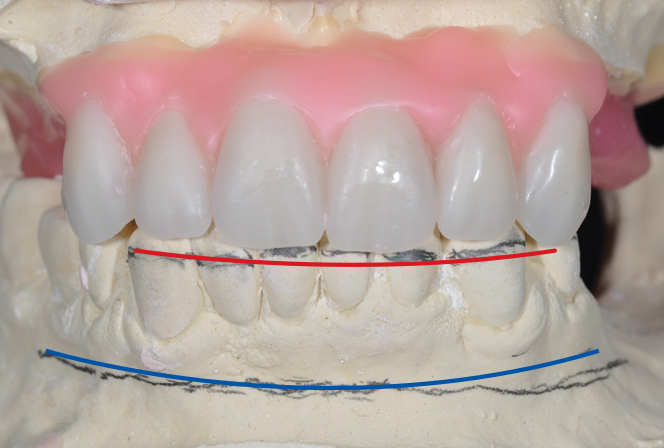

An important advantage of this approach is the ability to simulate bone reduction on the models and verify the presence of 15 mm to 17 mm and 13 mm to 15 mm of required inter-occlusal space for maxillary and mandibular restorations, respectively. This creates a platform for a diagnostic wax-up of the proposed dental rehabilitation and fabrication of wax prosthesis try-ins when necessary. Finally, a modified All-on-4 provisional prosthesis surgical and restorative guide developed by the authors for restoration-driven surgery and simplified restorative procedures is fabricated (Figure 2 through Figure 8).

Fig 3. Desired changes in the incisal plane are marked on the diagnostic models.

Figure 3

Fig 4. Diagnostic wax-up performed after model surgery simulating maxillary tooth extraction. Note that inferior repositioning of the incisal plane helped create the 15 mm to 17 mm inter-occlusal space needed for the maxillary All-on-4 provisional restoration.

Figure 4

Fig 5. Bone reduction model surgery performed in mandibular arch to create 13 mm to 15 mm of inter-occlusal space required for the mandibular All-on-4 provisional restoration.

Figure 5